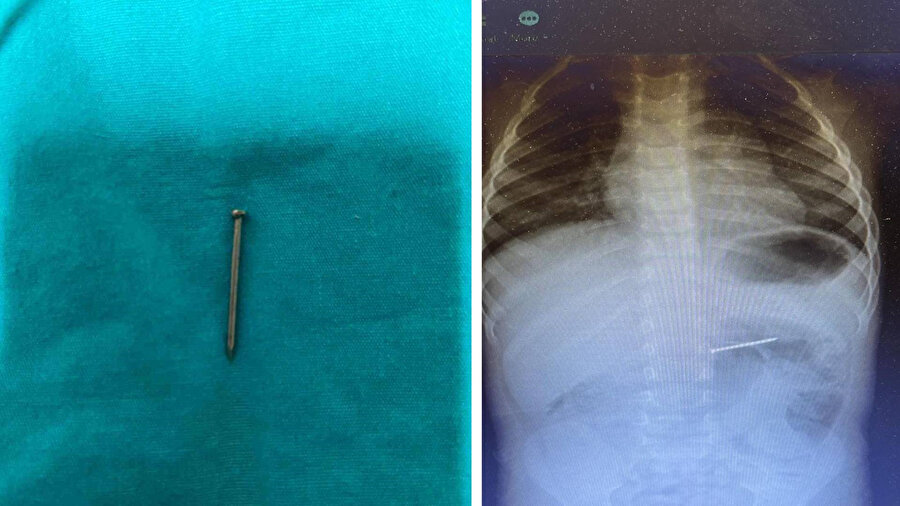

Burdur’un Bucak ilçesinde yaşayan 2 yaşındaki bir çocuk, yuttuğu çivi nedeniyle ailesi tarafından acil sağlık ekiplerine bildirildi. 112 Acil Servis aracılığıyla Süleyman Demirel Üniversitesi (SDÜ) Hastanesi’ne sevk edilen çocuk, Çocuk Gastroenteroloji ve Endoskopi Birimi’nde değerlendirmeye alındı. Radyolojik inceleme sonucu yaklaşık 4 santimetre uzunluğundaki çivinin midedeki konumu tespit edildi ve hemen endoskopik müdahale yapıldı. Yapılan işlemle çivi, herhangi bir komplikasyona yol açmadan başarılı şekilde çıkarıldı. Hasta, kısa süreli gözlem amacıyla serviste takip altına alındı ve sağlık durumu stabil şekilde taburcu edildi.